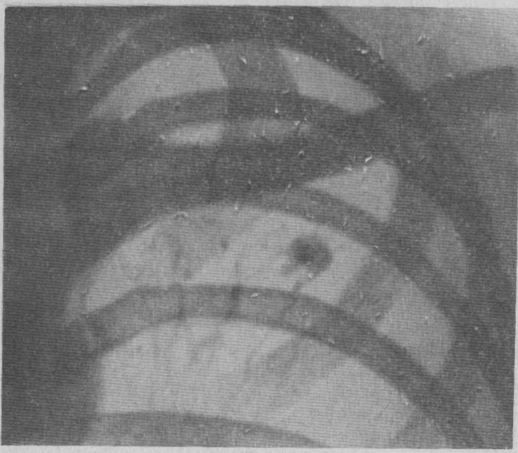

Иллюстрации по теме очагового и инфильтративного туберкулеза